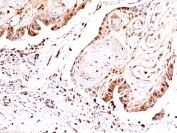

This antibody reacts to human JNK1, JNK2, and JNK3 only when phosphorylated at Thr183 and Tyr185.

The stated application concentrations are suggested starting points. Titration of the recombinant phosphorylated JNK antibody may be required due to differences in protocols and secondary/substrate sensitivity.

A phospho-peptide corresponding to human Phospho-JNK1/2/3 (Thr183/Tyr185) was used as the immunogen for the recombinant phosphorylated JNK antibody.